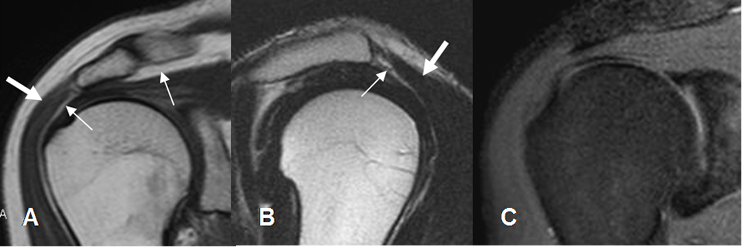

Fig 19. Tendinitis del supraespinoso.

A: RM coronal en T1. Aumento en la señal del tendón supraespinoso.

B: RM coronal en T2 y C: RM coronal en STIR. El supraespinoso es hiperintenso, irregular y rodeado por líquido, por tendinitis

La atrofia del músculo supraespinoso es un signo de cronicidad y se correlaciona con el resultado quirúrgico. (2). Se valora con el signo de la tangente, en un corte sagital. El supraespinoso debe cruzar la línea trazada entre el borde superior de la coracoides y la espina de la escápula. En casos de atrofia, el borde superior del músculo, se localiza inferior a esta línea. (2). (Fig 20).

Fig 20. Signo de la tangente.

A: RM sagital en T2. Supraespinoso normal, cruzando la línea tangente.

B: RM sagital en T2. Supraespinoso atrófico, por debajo de la línea tangente.